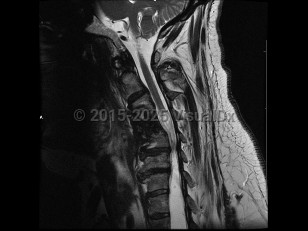

Syringomyelia is a cavity or syrinx within the spinal cord that can expand over time. Although the underlying pathophysiology is incompletely understood, syringomyelia is thought to form because of abnormal flow of the cerebrospinal fluid (CSF), and this dysfunctional pressure gradient causes fluid to build up in the spinal cord. Acquired syringomyelia may result from hydrocephalus, infection, inflammation, trauma or spinal cord injury, intramedullary or extramedullary tumors, spinal canal stenosis, vascular malformations, or bony abnormalities. Overall, the prevalence of syringomyelia varies worldwide, ranging from approximately 2-8 per 100 000. Age of onset varies by cause.

Symptoms depend on the location of the lesion; most occur in the cervical region, between C2 and T9. In some cases, patients are asymptomatic, and syringomyelia is an incidental finding on imaging. Cervical syringomyelia typically manifests as early impairment of temperature and pain sensation in a cape-like distribution over the back and arms, and weakness that is greater in the bilateral upper extremities compared with the bilateral lower extremities. There may also be chronic pain. Neurologic examination may be notable for loss of reflexes, light touch, vibration, and joint position sense; weakness and atrophy of the hands; and lower extremity spasticity and hyperreflexia. Bladder, bowel, and erectile dysfunction can occur as late manifestations.